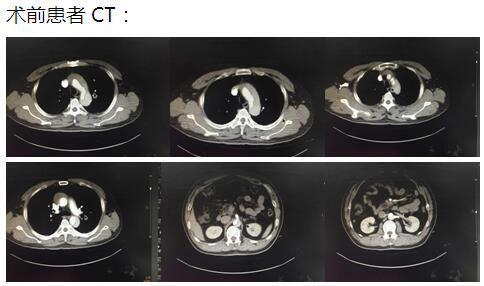

患者是一位48歲中年男性,因胸痛1小時(shí)入院,我院CT提示主動(dòng)脈夾層累及胸、腹主動(dòng)脈全層,診斷為主動(dòng)脈夾層(D ebaKey I型)。患者病情危重,手術(shù)治療是挽救其生命的唯一希望。為了挽救病人生命,經(jīng)過麻醉科、手術(shù)室、體外循環(huán)組的術(shù)前充分討論,心胸外科廖金文主任、廖承輝副主任帶領(lǐng)團(tuán)隊(duì)決定為其施行復(fù)雜而高難度的淺低溫停循環(huán)下“孫氏手術(shù)”。術(shù)中見主動(dòng)脈全程及三分支受累,右冠受累,冠脈開口受壓狹窄,予以行“升主動(dòng)脈 主動(dòng)脈弓置換 降主動(dòng)脈術(shù)中支架置入術(shù)”,團(tuán)隊(duì)成員歷經(jīng)約10個(gè)小時(shí)的奮戰(zhàn),手術(shù)順利完成。術(shù)后六小時(shí)患者意識(shí)完全清醒,現(xiàn)在已完全康復(fù)。